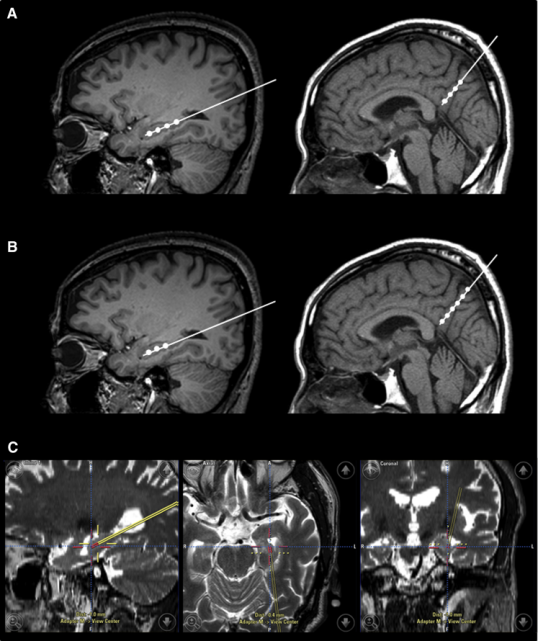

- 腦成像測試,如頭部CT掃描或頭部MRI

2015年,韓國首爾三星醫療中心招募了9名輕度至中度癡呆的阿爾茨海默氏病患者。Kim對9名患者進行了一項立體定向注射間充質干細胞的I期臨床試驗。

三名患者接受低劑量(1.0×107細胞/2 mL),6名患者接受高劑量(3.0×107hUCB-MSC 的細胞/2 mL) 。9名患者進行了三次干細胞注射(每隔4周一次)。

在之后長達36個月的跟蹤研究期間, 沒有患者出現嚴重的不良事件。由此可見, 干細胞治療阿爾茲海默癥是可行、安全且耐受性良好的。

2a期試驗被命名為CLEAR MIND試驗,于2021年12月底開啟。實驗共納入了50位患者(49名接受治療),年齡在60-85歲之間,按美國國立衛生研究院-阿爾茨海默氏癥協會(NIA-AA)的標準,他們都是輕度阿爾茨海默氏癥患者。

這一次,研究測試了三種劑量的Lomecel-B與安慰劑,主要測試終點還是安全性,次要終點則是復合阿爾茨海默癥評分(CADS)從基線到第39周的變化,探索性終點包括腦容量測試、認知功能測試等等。

經過近兩年的研究,2023年10月,Longeveron公司宣布了2a期試驗結果。靜脈輸注間充質干細胞可將輕度患者腦部與AD相關的腦容量損失減少49%!

臨床結論:2a期臨床研究報告顯示,細胞治療可將患者腦部與AD相關的腦容量損失減少49%,并能減輕腦神經炎癥,改善腦血流量與認知功能。這些數據進一步證實了間充質干細胞在治療AD上的潛力,為患者們帶去了新的希望。